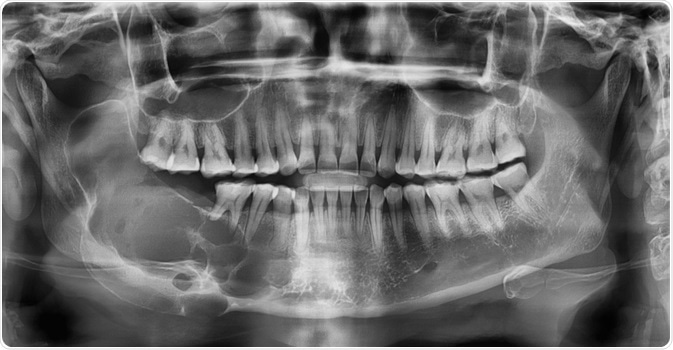

Ameloblastoma

Image Credit: Rames Khusakul/Shutterstock.com

A combination of both clinical examination and an X-ray is commonly used to diagnose suspected ameloblastoma. Referral to an Oral and Maxillofacial Surgeon for a second opinion and confirmation of the diagnosis is fairly usual. Many ameloblastomas are discovered by chance at the dentist during ordinary dental operations or X-rays.

When a tumor seems to be an infection, causing discomfort and swelling in the jaw, it is usually treated with antibiotics. When antibiotics fail to ease the symptoms, a regular X-ray is taken to further check the symptoms, and the probable ameloblastoma is discovered. Further tests including CT scans, MRI scans, and a biopsy of the bone are used to confirm the presence of the tumor.